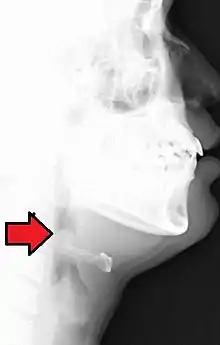

| Neck X-ray showing thumbprint sign. | |

Epiglottitis was historically mostly caused by infection by H. influenzae type b (commonly referred to as "Hib").[1] With vaccination, it is now more often caused by other bacteria, most commonly Streptococcus pneumoniae, Streptococcus pyogenes, or Staphylococcus aureus.[1] Predisposing factors include burns and trauma to the area.[1] The most accurate way to make the diagnosis is to look directly at the epiglottis.[3] X-rays of the neck from the side may show a "thumbprint sign" but the lack of this sign does not mean the condition is absent.[1]

On lateral C-spine X-ray, the thumbprint sign describes a swollen, enlarged epiglottis.[10] A normal X-ray, however, does not exclude the diagnosis.[10] An ultrasound may be helpful if specific changes are present, but its use (as of 2018) is in the early stages of study.[10]